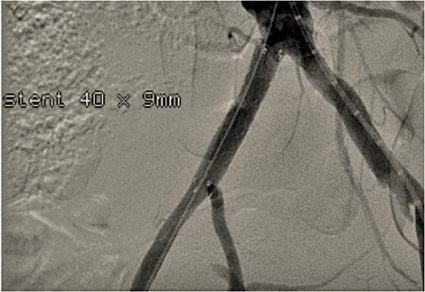

Kirurgisk/endovaskulär behanding

Invasiv behandling av benartärsjukdom innefattar dels öppen kirurgi (t ex bypass, trombendarterektomi), dels endovaskulär intervention (perkutan angioplastik, PTA, med eventuell stentning). Under 2009 utfördes i Sverige ca 3 500 infrainguinala ingrepp (öppna och endovaskulära); 60 procent av dessa på indikationen claudicatio. Det finns endast begränsad evidens för effekt av invasiv behandling vid claudicatio (till skillnad från vid kritisk ischemi).

Endovaskulär behandling av claudicatio har undersökts i flera studier. En multicenterstudie [33] visade att PTA vid både supra- och infrainguinal sjukdom hade en adjuvant effekt på den absoluta gångsträckan hos patienter som redan erhållit riskfaktormodifiering och gångträning. Ytterligare en studie [25] visade på snabbare klinisk förbättring efter PTA jämfört med strukturerad gångträning. Effekten var dock inte lika stor i båda grupperna efter ett år.

Endovaskulär behandling (PTA med eller utan stent) av suprainguinala lesioner ger en utmärkt öppetståendefrekvens (patency) på både kortare och längre sikt och bör vara förstahandsalternativ när anatomiska förutsättningar finns. Andra alternativ är aortobifemoral bypass och axillobifemoral bypass. Det förstnämnda ger en mycket god öppetståendefrekvens men är ett stort kirurgisk ingrepp med större risk för peroperativa komplikationer. Det senare utförs sällan på indikationen claudicatio på grund av sämre öppetståendefrekvens och ökad risk för bl a graftinfektion.

Vid infrainguinal sjukdom är öppetståendefrekvens- och komplikationsprofilen för både öppna och endovaskulära åtgärder inte lika gynnsamma som vid suprainguinal sjukdom. Vid claudicatio är tröskeln för behandling något högre. PTA ger vid korta, enstaka eller multipla lesioner i a femoralis superficialis (SFA) god öppetståendefrekvens och är enligt de senaste TASC-riktlinjerna [10] förstahandsalternativ. Vid långsträckta kroniska SFA-ocklusioner, där återfyllnad sker i antingen poplitea ovan eller nedom knäleden, kan femoropopliteal bypass vara ett alternativ om tillgång till egen ven finns då syntetgraft ger betydligt sämre öppetståendefrekvens. Mer långsträckta lesioner och lesioner som involverar trifurkationen ger sämre behandlingsresultat både öppet och endovaskulärt, och behandling i dessa kärlsegment förbehålls oftast patienter med kritisk ischemi.